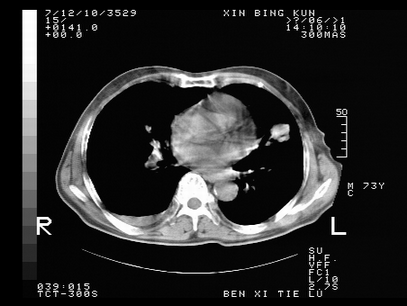

标题: CT10820:男,73岁,病史肺TB,现病史肺炎,直肠CA术后 [打印本页]

标题: CT10820:男,73岁,病史肺TB,现病史肺炎,直肠CA术后

双肺间质改变,依据病史双肺多发结节灶考虑转移,少量胸水.

1.两肺结核.2.两肺多发转移瘤.3右侧少量胸腔积液4.主动脉钙化.

双肺多发结节及条片状致密影,右侧少量胸腔积液。临床:直肠ca术后,肺tb病史。综合考虑:1 双肺转移!2 继发性肺结核合并感染!

此人病史较复杂,原有肺结核,直肠癌术后。肺部病灶形态亦呈多形性。因此,不可仅以一种病来解释肺部的病变。双肺多发的类圆形结节灶,结合病史还是首先考虑转移瘤,而双肺其余病灶还需结合化验室检查,结核或肺部感染在无其它检查资料的情况下不好排除。还是那句话----放射科医生不是开照像馆的,我们也是医生,看片一定要多结合临床及其它检查资料。要当一名合格的放射科医生,并不比当一名临床医生容易,我们可别把自已不当医生看。

两肺多发结节影,并见滋养动脉与其相连,考虑 两肺转移. 右侧胸腔积液考虑胸膜转移.

左肺上叶下叶背段,右肺中下叶见多发斑片状、条索状高密度影,兵变周围小结节影形成“树芽”样改变。 左肺上叶舌段近前胸壁处及右肺中叶内侧段见结节影。右侧胸膜腔内见液体密度区。纵隔内未见明确增大淋巴结。考虑左肺上叶舌段近前胸壁处及右肺中叶转移瘤可能性大。两肺继发型肺结核。右侧胸腔积液。

还有心包少量积液。